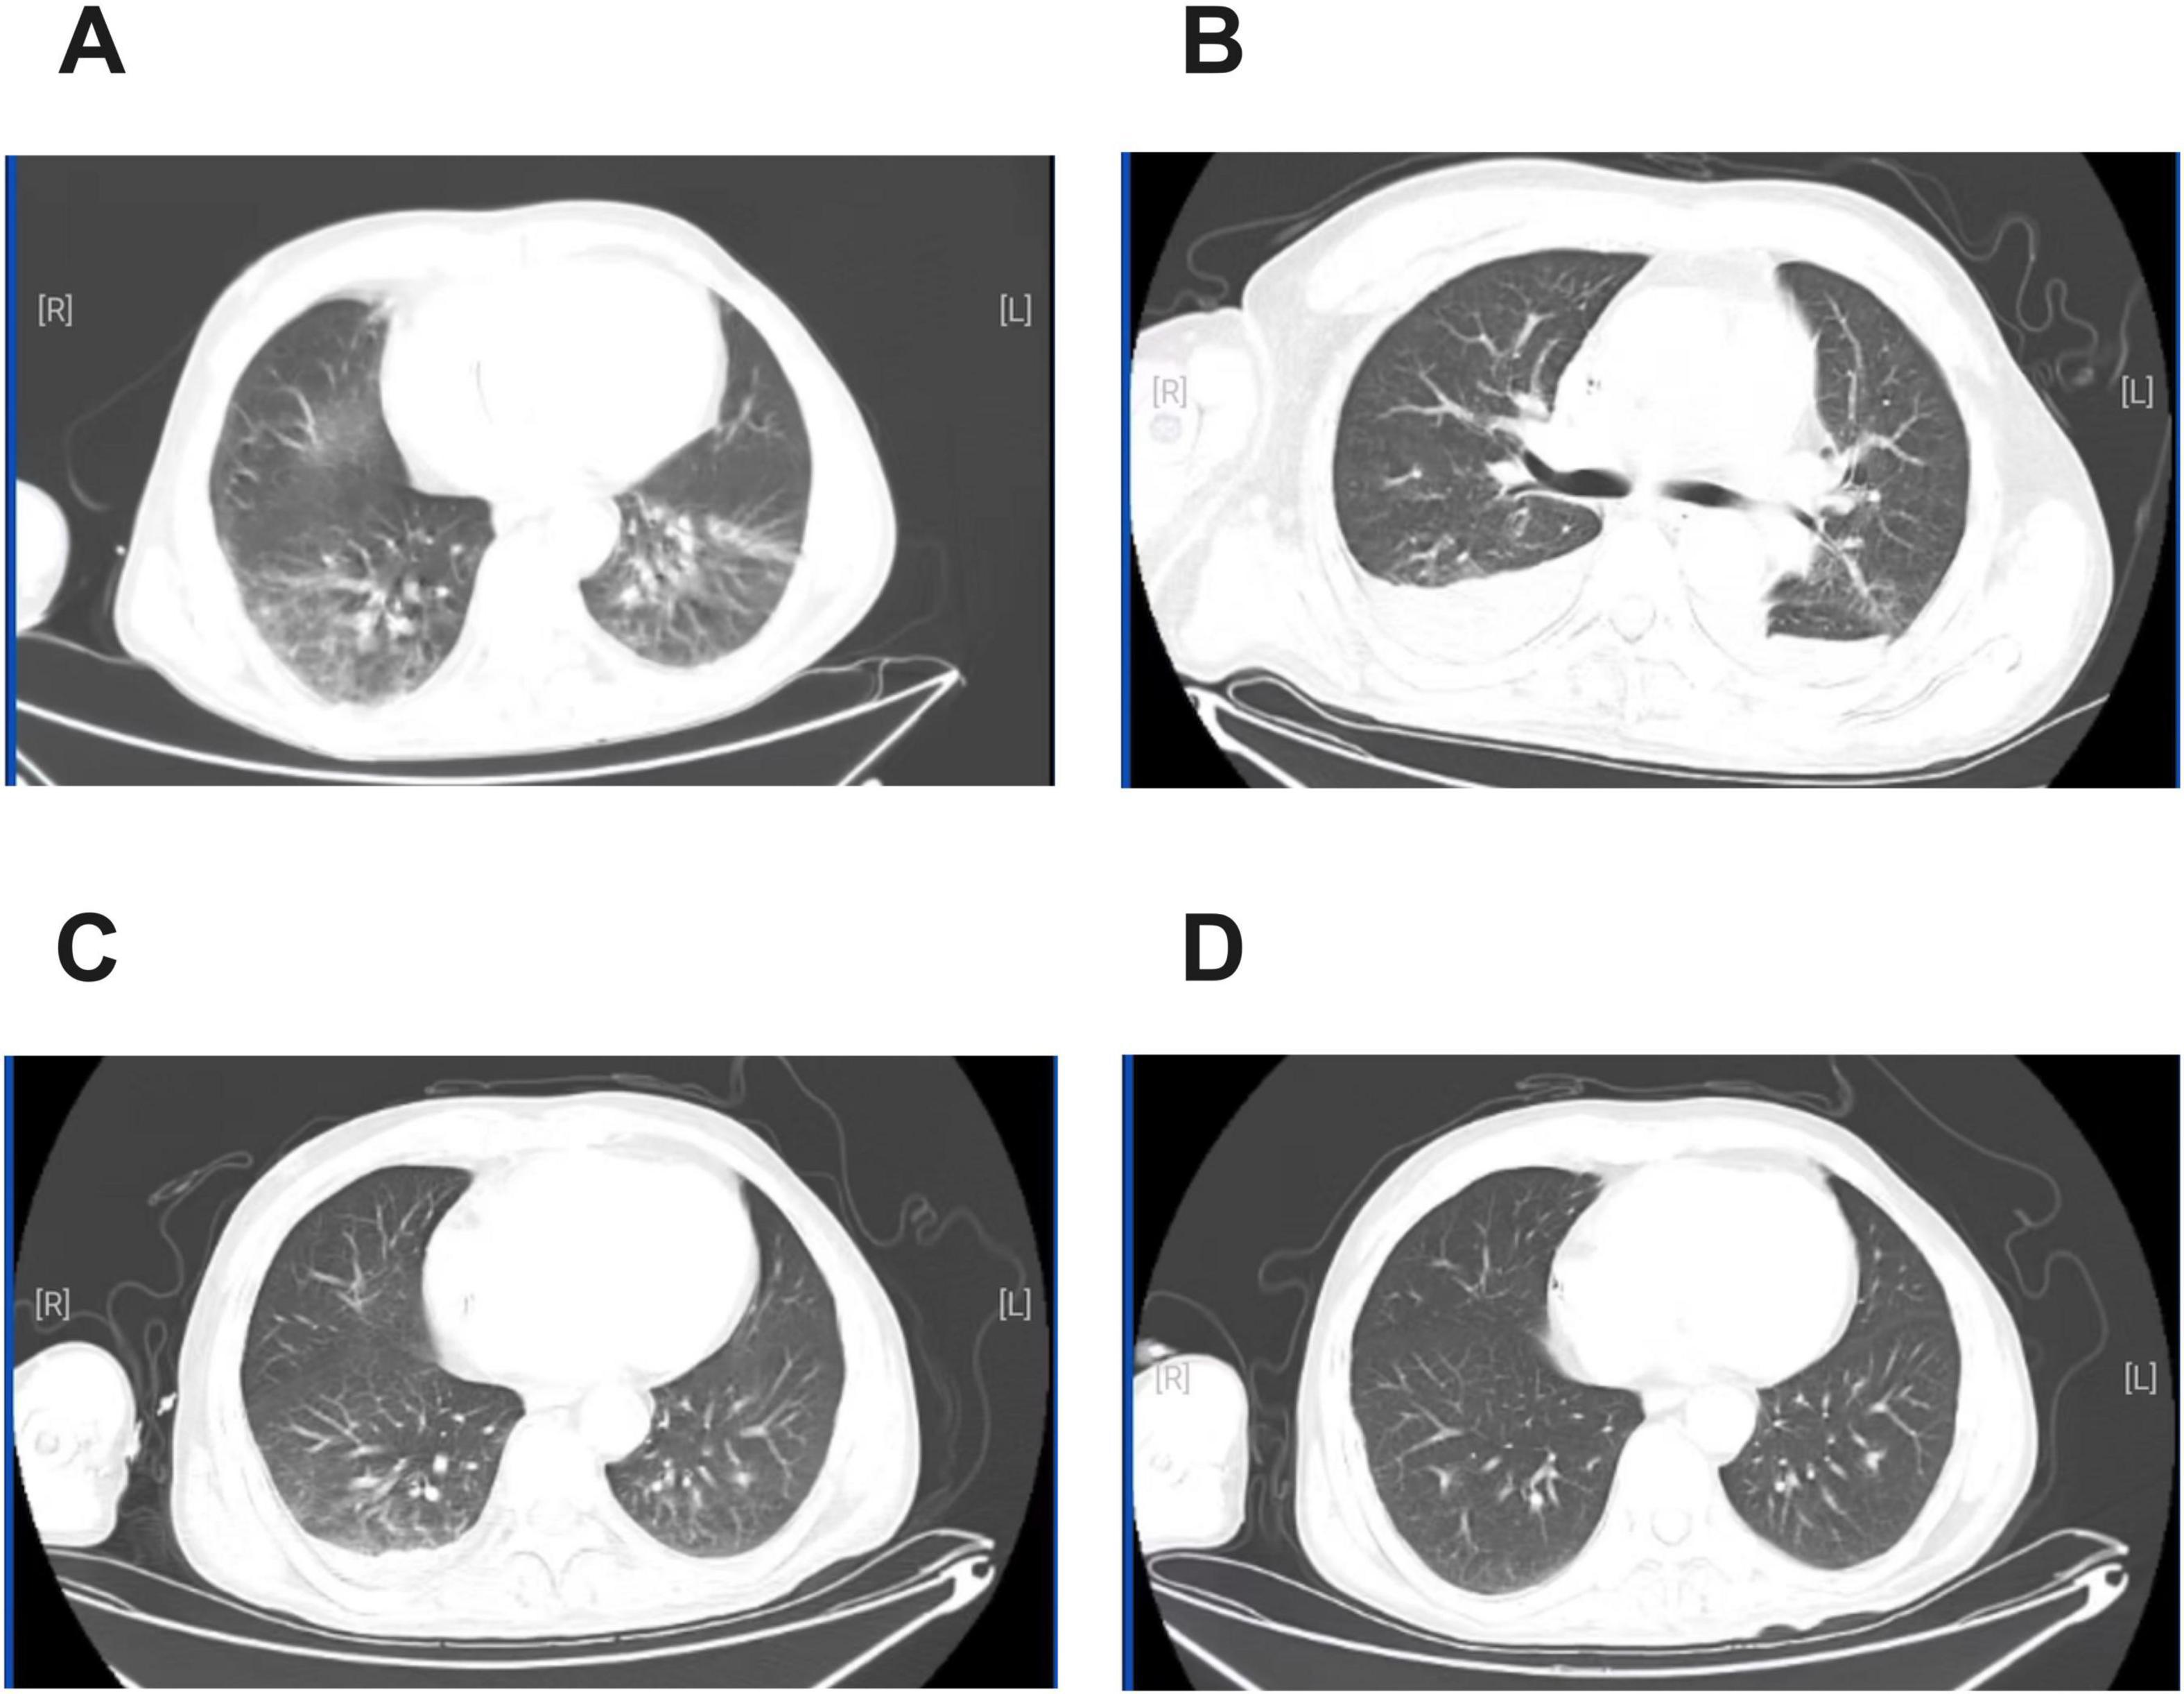

The patient was a 55-year-old man weighing 56.5 kg. BMI was 18.66 kg/m2. He was diagnosed with diffuse large B-cell lymphoma five months previously and was undergoing regular chemotherapy. He was admitted to our hospital with fever for 3 days. His vital signs were as follows: temperature 39°C, blood pressure 87/50 mmHg, pulse 108 beats/min, and respiratory rate 26 breaths/min with an oxygen saturation of 95% on room air. Laboratory examination showed white blood cell count (WBC): 3.9 × 109/L, the proportion of neutrophils was 76.9%, C-reactive protein (CRP): 189.3 mg/L, Procalcitonin (PCT): 4.46 ng/mL, creatinine: 366.5 μmol/L, eGFR: 16.12 mL/min (Table 1). Chest Computed Tomography (CT) was obtained, showing streaks, nodules and patchy abnormal shadows in both lungs (Figure 1A). The patient was diagnosed with septic shock. Blood and sputum cultures were obtained and the patient was initially empirically treated with imipenem (0.5 g q8h iv) for 5 days. On day 6 of treatment (D6), the temperature was 39°C, WBC count was 6.88 × 109/L, the proportion of neutrophils was 92.6%, the CRP level was 63.17 mg/L, PCT decreased to 2.098 ng/mL, the creatinine was 156.7 μmol/L (Table 1). The follow-up CT scan revealed reticular shadows, nodules, patchy infiltrates, and areas of consolidation in both lungs with ill-defined margins; atelectasis in the lower lobes of both lungs, and bilateral pleural effusion (Figure 1B). Blood aerobic culture was positive on the automatic blood culture system. The identification was performed by MALDI-TOF MS (Autof MS 1000), confirming the isolate as Nocardia cyriacigeorgica. The confidence score was 99.9%. Due to challenges associated with antimicrobial stability and the fastidious growth characteristics of Nocardia spp., most clinical laboratories in China do not routinely perform susceptibility testing. The antibiotic regimen was changed to imipenem (0.5 g q6h iv), linezolid (0.6 g q12h iv) and trimethoprim-sulfamethoxazole (TMP-SMX) (160 mg/800 mg bid) for 23 days (13). After counseling on risks of undiagnosed intracranial pathology, the patient declined brain imaging studies due to absence of symptoms suggestive of intracranial infection (13, 14). After 3 days of treatment (D9), the patient’s temperature was around 38°C. Neutrophil%, CRP, PCT and creatinine decreased (Table 1). On D14, the patient’s clinical condition improved. A repeat blood culture was negative. On D22, chest CT showed significant reduction in the lesion area (Figure 1C). The patient’s temperature was normal. On D29, the result of chest CT was bilateral pulmonary nodules (Figure 1D). The patient was afebrile. The patient was discharged from the hospital on the 30th day after the admission. There were no adverse drug reactions observed during treatment. After discharge, the patient was asked to continue oral TMP-SMX and repeat chest CT imaging regularly (clinical course summarized in Figure 2).

FIGURE 1

CT of the chest. (A) Admission. (B) After 6 days of treatment with imipenem. (C) After 16 days of treatment with imipenem, linezolid and TMP-SMX (D). After 23 days of treatment with imipenem, linezolid and TMP-SMX.